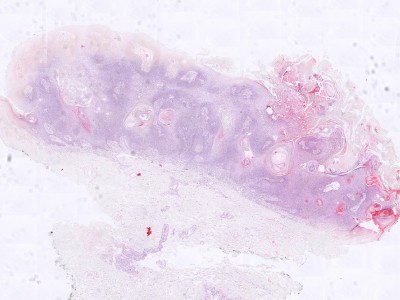

Histologie:Het histologisch beeld wordt gekenmerkt

door een scherp begrensde exofytisch of endofytisch groeiende tumor. Meestal

is er hyperkeratose en een papillomateus verbrede epidermis. De hyperkeratose

en de neiging van de retelijsten om te vergroeien, hebben de vorming van pseudo-hoorncysten

tot gevolg. De tumor is opgebouwd uit opvallend kleine spinale cellen. Basale

hyperpigmentatie is er in een derde van de gevallen. De epidermis toont geen

cytonucleaire atypie. Meestal zijn er geen afwijkingen in de dermis. In de dermis

van een geirriteerde verruca seborrhoica wordt echter een uitgebreid rondkernig

ontstekingsinfiltraat gezien met grensvlakactiviteit en soms met dyskeratotische

keratinocyten. Karakteristiek zijn de zogenaamde “squamous eddies”, nesten van

keratinocyten. Het Borst-Jadassohn type, ookwel het clonale type, is te herkennen

aan intra-epidermale nesten van spinale cellen.